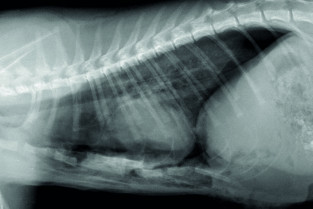

Le GEIM vous propose une séance de travaux pratiques de radiographies sur le thorax. Tous les aspects sont abordés sous la forme de TP de lecture de radiographies numériques sur station de travail Osirix sur Mac (3 vétérinaires maximum/ordinateur).

- adopter une méthodologie pour interpréter les affections pulmonaires chez les carnivores domestiques ;

- décrire l’aspect normal et anormal des poumons chez les carnivores domestiques.